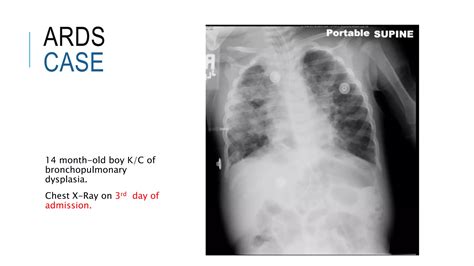

ARDS is a complex syndrome that can be triggered by various factors, including sepsis, pneumonia, trauma, and aspiration. It is marked by the rapid onset of bilateral pulmonary infiltrates, refractory hypoxemia, and decreased lung compliance. The Ards Chest X Ray is instrumental in visualizing these pulmonary infiltrates, which appear as diffuse, bilateral opacities on the radiograph.

The Ards Chest X Ray is often the first imaging modality used to evaluate patients suspected of having ARDS. It provides a quick and relatively inexpensive way to assess the lungs for signs of inflammation and edema. Key findings on an Ards Chest X Ray include:

• Bilateral pulmonary infiltrates

• Diffuse opacities

• Air bronchograms (air-filled bronchi surrounded by consolidated lung tissue)

• Absence of pleural effusions or cardiomegaly

These findings, when combined with clinical criteria such as the PaO2/FiO2 ratio (the ratio of arterial oxygen partial pressure to fractional inspired oxygen), help confirm the diagnosis of ARDS.

• Bilateral Infiltrates: ARDS typically presents with bilateral, diffuse infiltrates that are often more pronounced in the dependent lung zones.

• Air Bronchograms: These are visible air-filled bronchi within consolidated lung tissue and are a hallmark of ARDS.

• Absence of Pleural Effusions: Unlike other causes of pulmonary edema, ARDS is usually not associated with significant pleural effusions.

• Cardiomegaly: The heart size is typically normal in ARDS, helping to differentiate it from cardiogenic pulmonary edema.